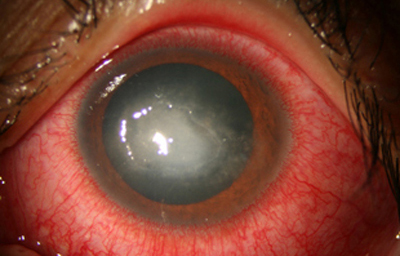

Superficie corneal irregular y grisácea, (Fig. 1, 2) con opácidades granulares en parche y formación de líneas epiteliales elevadas de aspecto granular (Fig. 3), que pueden arborizar dando imágenes de pseudodendritas. Opacidades superficiales satélites. (Figura 4) Inyección ciliar. Ulceración epitelial variante. (Figura 5).

En su evolución se observará aumento del edema, agrandamiento y coalescencia de los infiltrados formando un anillo, (Figura 9, 10 y 11) que progresa hacia la formación de un absceso (Figura 12, 13 y 14), queratolisis superficial, adelgazamiento y perforación corneal (Figura 15 y 16).

Limbitis y escleritis anterior difusas.

La vascularización y el hipopion son poco frecuentes en los estadios tempranos de la queratitis. Con el tiempo, en los estados avanzados de invasión estromal, aparecen vasos estromales (Figura 17)

En los estados avanzados con abscesificación y queratolisis, se enmascara el cuadro corneal, ocultando las características clínicas típicas de la queratitis por Acanthamoeba. (Fig 18)